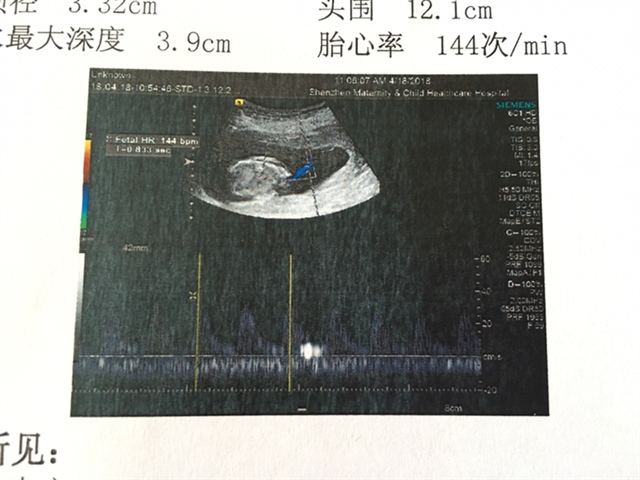

孕12周+6天

孕13周+6天